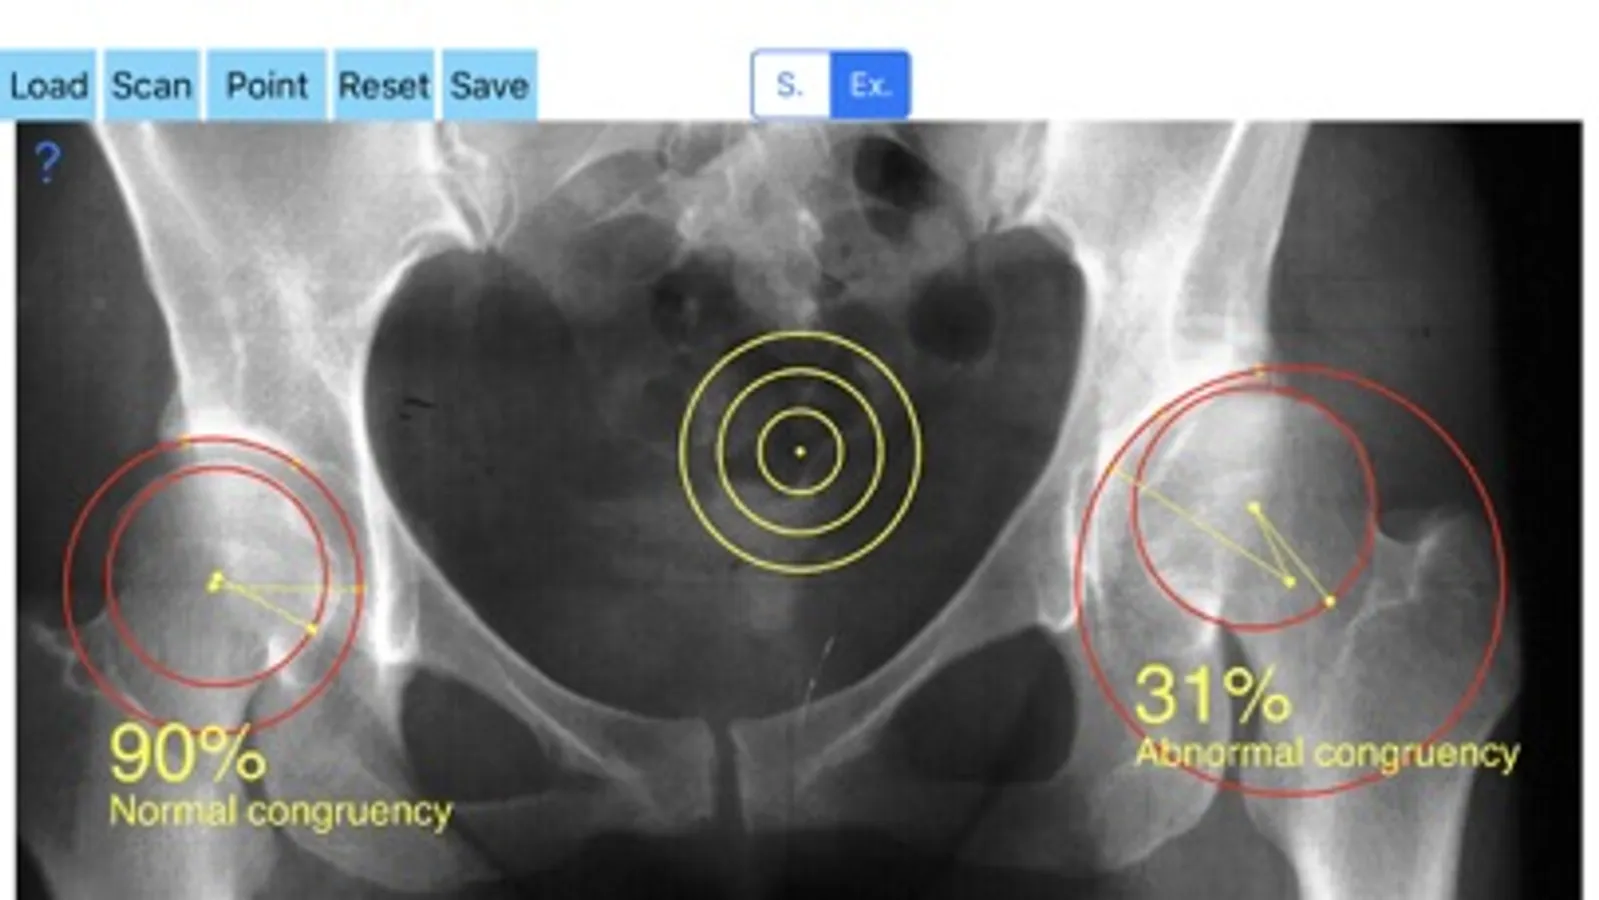

-Offers a very convenient and most accurate possibly way to determine joint space congruency with two methods. With transparent circular template-Moses template- you try to find the best-fitted circle superimposed over the femoral head, you mark the femoral head center and with the same manner you locate the acetabular center of the weight bearing zone. When the center of the best-fitted circle of the acetabulum coincide with the center of the femoral head, the concruency of the joint is considered normal (CnI =100%).The app calculates automatically the congruency index. The results are printed as a percentage of congruency of the hip joint and the hip is categorized as normal or abnormal.

Congruence is present when the center of the femoral head (ball) and that of the acetabulum (socket) coincide. Lack of hip congruence between the femoral head and the acetabulum leads to increased local contact stresses, degeneration and consequently to premature arthritis. Although corrective hip osteotomies for the realignment of the dysplastic acetabulum is the main goal of treatment strategies, if the joint space congruency remain fair this end up in failure. Joint congruency can be rated subjectively according to the surgeons experience but according to international literature, evaluation and monitoring hip joint congruency is crucial to judge and predict the outcome of treatment. The App measures objectively the congruence and gives values as percentage (Congruence Index) which can be used for evaluation or comparisons of treatments modalities like acetabular osteotomies in developmental dysplasia or Legg-Calve-Perthes disease of the hip.